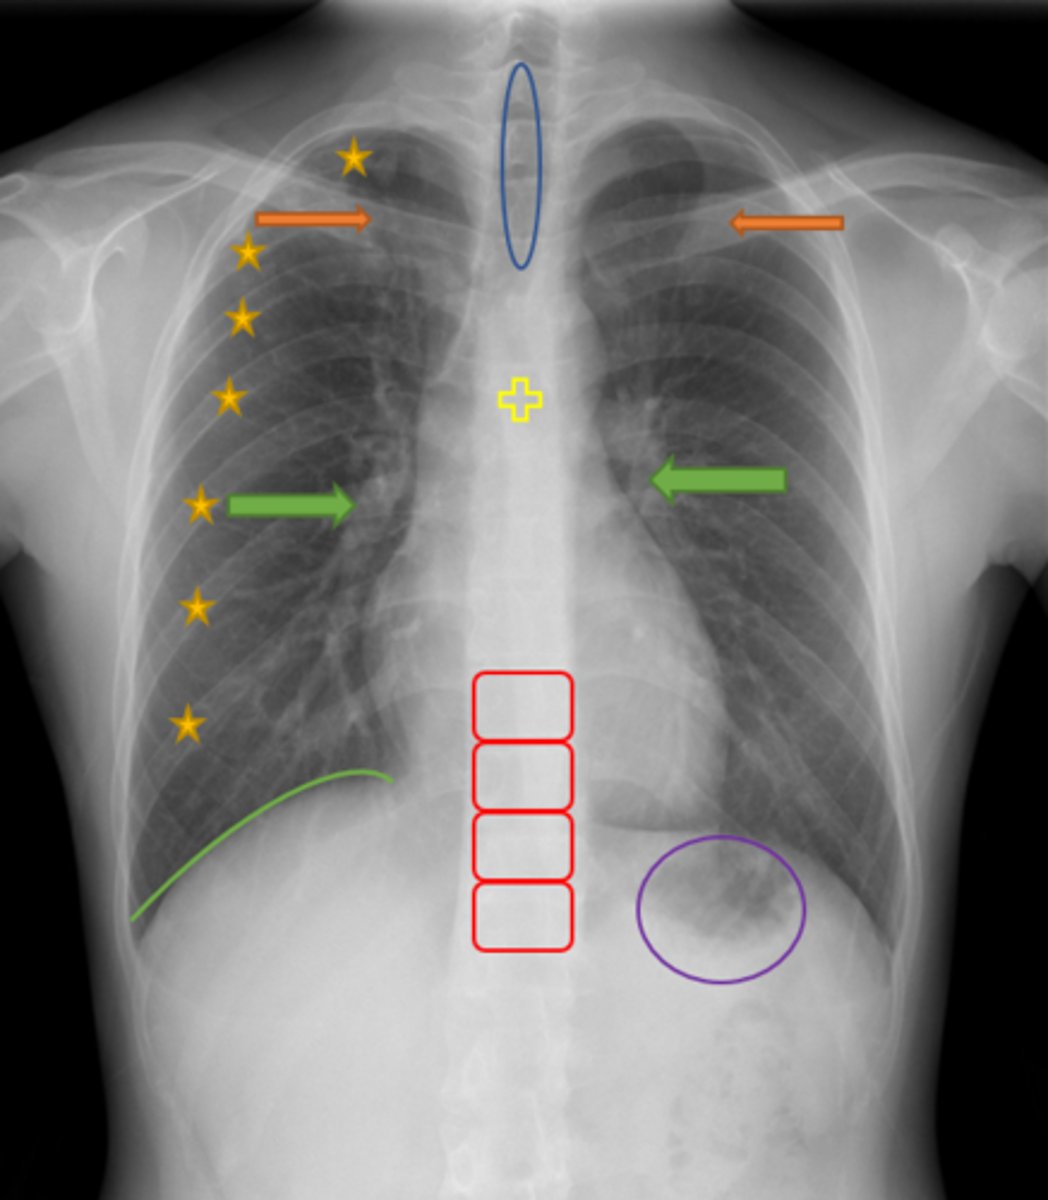

Aortic knob/arch

Pink Arrow

Left ventricle and border of the heart

Purple Line

Pulmonary arteries

Blue Arrows

Normal film

Interpretation

Trachea

Blue Oval

Pulmonary arteries

Green Arrows

Vertebrae/spine

Red Blocks

Clavicle

Orange Arrows

Ribs

Yellow Stars

Diaphragm

Green Line

Gastric bubble/stomach

Purple Circle

Carina

Yellow Cross